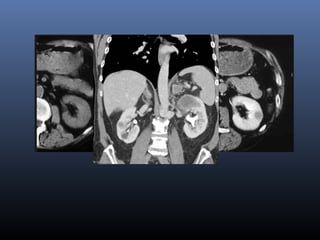

CT: thành phần mỡ cùa tổn thương

(IV-) ; đậm độ MỠ (-20 UH)

Không có đóng vôi

AML